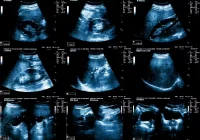

Ultrasound is highly effective in detecting parathyroid adenomas, the most common cause of primary hyperparathyroidism. Typical adenomas appear as well-defined, hypoechoic lesions with distinctive vascular patterns, such as polar feeding vessels and peripheral arclike flow. The use of high-frequency transducers and Doppler imaging improves sensitivity, especially for lesions under 1 cm. Newer techniques like contrast-enhanced ultrasound and elastography offer additional diagnostic confidence, particularly in distinguishing adenomas from thyroid nodules or lymph nodes.

Parathyroid adenomas, usually solitary and benign, account for the vast majority of primary hyperparathyroidism cases. Sonographic features often include uniform hypoechogenicity and intense vascularity. Atypical cases may appear cystic, isoechoic or heterogeneous. In some patients, double adenomas or multigland hyperplasia are present, necessitating broader evaluation and surgical consideration.

Accurate diagnosis also requires distinguishing parathyroid lesions from mimics. Thyroid nodules, lymph nodes and other structures like the esophagus or longus colli muscle can exhibit overlapping imaging features. Recognising differences in vascular patterns, echogenicity and anatomical continuity helps avoid misdiagnosis. For example, the presence of a polar feeding artery and peripheral arclike vascularity favours a parathyroid adenoma over a thyroid nodule or lymph node.